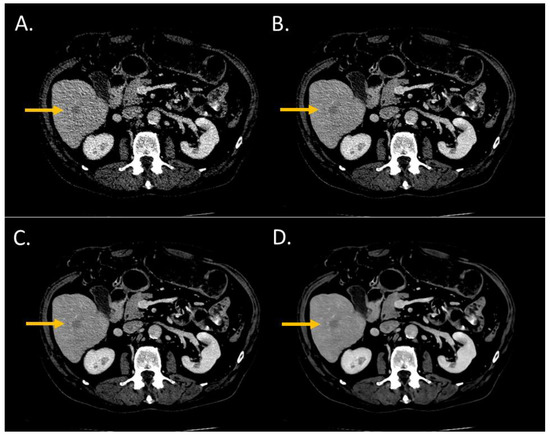

The conspicuity score significantly increased from i4 to the Standard level and from the Standard to the Smoother level (p < 0.05) (Figure 2 and Figure 3). The conspicuity score was ≥4 for 37% with i4, 53% for the Standard, 80% for the Smooth, and 93% for the Smoother level.

Figure 2.

Lesion conspicuity score of liver CT images (WL: 90 HU; WW: 190 HU) of a man (64 years old, SSDE: 6.73 mGy; average scan size 28.9 cm) with colorectal cancer and a liver metastasis of 14.1-mm diameter in the segment VI. (A) iDose4 level 4; lesion conspicuity score: 3; (B) Precise Image, Standard; lesion conspicuity score: 3; (C) Precise Image, Smooth; lesion conspicuity score: 4; (D) Precise Image, Smoother; lesion conspicuity score: 5.

Figure 3.

Lesion conspicuity score of liver CT images (WL: 90 HU; WW: 190 HU) of a man (64 years old, SSDE: 10.24 mGy; average scan size 34.6 cm) with a pancreatic cancer and liver metastasis of 2.70 mm of large axis in segment VIII. (A) iDose4 level 4; lesion conspicuity score: 3; (B) Precise Image, Standard; lesion conspicuity score: 3; (C) Precise Image, Smooth; lesion conspicuity score: 4; (D) Precise Image, Smoother; lesion conspicuity score: 5.